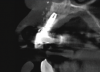

In this case, a dental implant that had been placed 10 years prior was functional, stable, and esthetically acceptable to the patient. However, a significant fistula was present on the facial-apical aspect of the ridge in the maxillary lateral incisor area. This area was painfully sensitive to touch and demonstrated purulence when squeezed. To evaluate the lesion, first, a conventional digital radiograph was acquired, which revealed an apical radiolucency at the apex of the implant (Figure 1). Further analysis using cone-beam computed tomography (CBCT) demonstrated a fistula from that site to the oral environment (Figure 2). Treatment options were discussed, including removal of the implant, followed by grafting, a healing period, and replacement of the implant and implant-retained crown. If this option was selected, a transitional appliance would need to be created. Another option was to attempt to salvage the implant and implant crown by treating the infection and grafting the site to create a new boney wall and eliminate the fistula. Ultimately, the patient accepted this option to attempt to salvage the fixture and crown.

(2.) Preoperative CBCT analysis demonstrating a fistula from the site of the radiolucency to the oral environment.

Figure 2